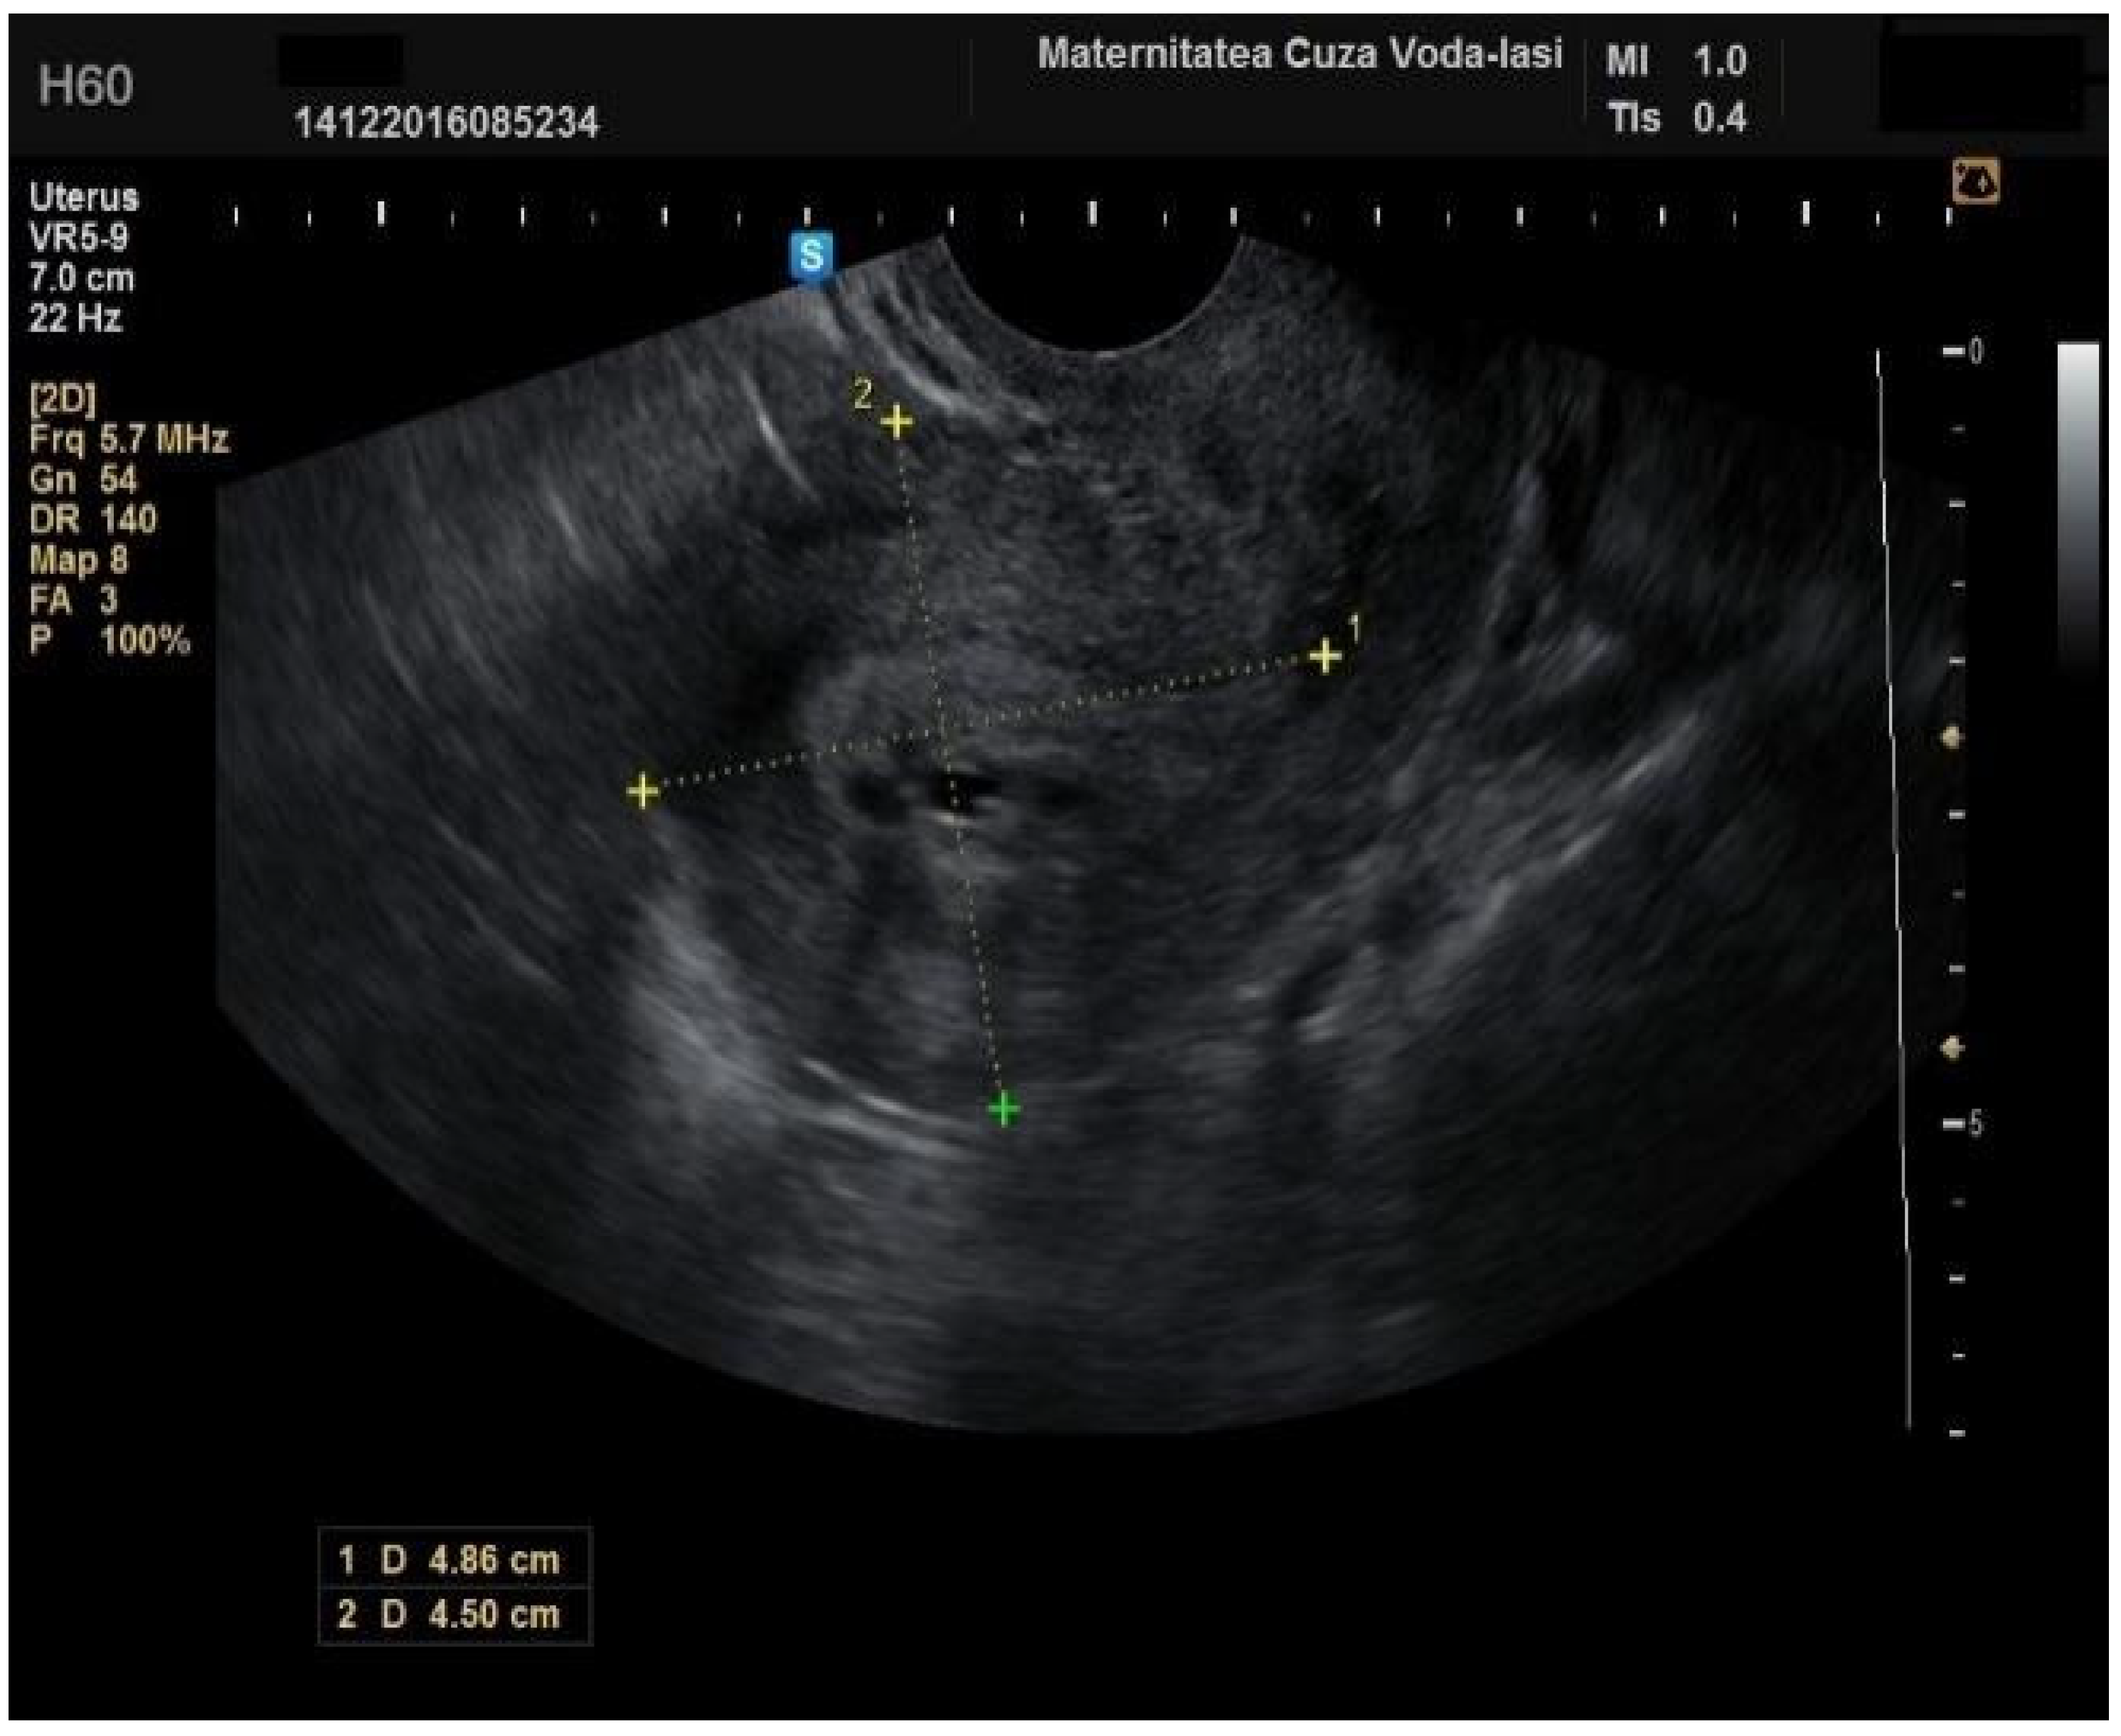

The average endometrial thickness, as measured by transvaginal ultrasonography, was found to be 18.02 ± 10.94 mm (range: 5–64 mm). Malignancy was identified in 22.84% of cases with uterine cavity findings. The mean endometrial thickness for women diagnosed with endometrial cancer was 24.49 ± 13.33 mm (95% confidence interval [CI]: 14.34 to 35.16), (Figure 2), whereas those with other pathologies had a mean thickness of 16.10 ± 9.37 (95% CI: 13.14 to 18.57), (Figure 3), with statistical significance (p = 0.028). When endometrial thickness was used as a standalone variable to build a model for estimating the risk for endometrial malignancy it demonstrated the highest AUC with a value of 0.682 (95% CI: 0.452–0.912). A cut-off threshold of 26 mm for endometrial thickness yielded a sensitivity of 62.5% and a specificity of 89% (Figure 4).

Figure 2. Ultrasonographic imaging of endometrial cancer.

Figure 13. Ultrasound imaging in endometrial cancer: invasion of the posterior myometrium extending less than 50%—without vascularization.